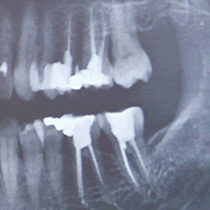

Bezpieczna i nowoczesna Pracowania RTG

Zapraszamy pacjentów do skorzystania z nowoczesnej stomatologicznej pracowni radiologicznej. Oferujemy wykonywanie zdjęć przeglądowych (pantomograficznych) oraz punktowych zębów. Dzięki zastosowaniu technologii cyfrowej dawka promieniowania jest kilkunastokrotnie mniejsza niż w przypadku tradycyjnych zdjęć wykonywanych na kliszy.

Możliwość wykonania tomografii szczęk, żuwchwy etc.

Informacja o wpływie działalności wykonywanej przez jednostkę organizacyjną polegającej na uruchomieniu pracowni rtg oraz uruchomieniu i stosowaniu aparatów rtg na zdrowie ludzi i na środowisko.